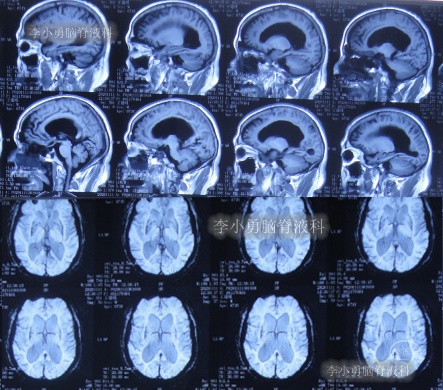

2021年5月5日(腰大池腹腔分流术后38天,即拔除硬膜下血肿引流管16天),查头部核磁和腰椎核磁(图-10、图-11)后认为可能是颅内感染或和堵管。

图-10:2021年5月5日头部核磁